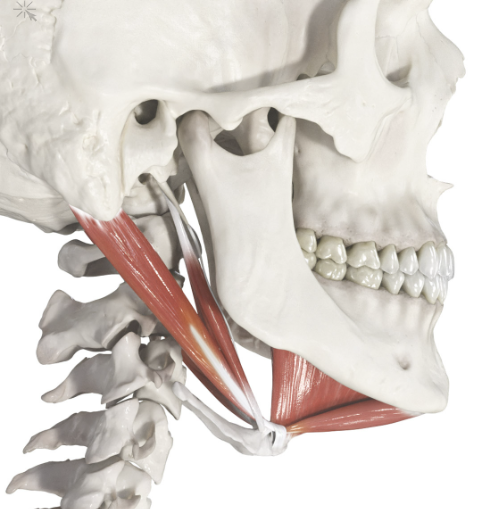

Okay so my hyoid bone is very low and i have a double chin even though im not high bf% im sub 19% im 170 cm and weigh around 60 kg.

Regardless my chin or mandible is recessed and if i get bimax or trimax wouldnt that also benefit my hyoid bone?

cuz if the mandible gets longer then shouldnt my hyoid bone go higher?